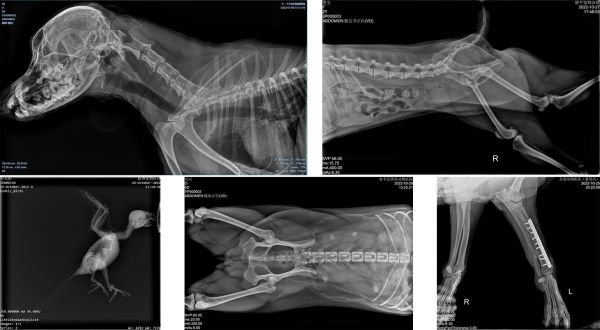

X光:拍一张透视照

当进行X光检查时,机器会发出X射线穿透全身,把身体各个部位的立体图像照在一张二维图上。由于骨骼、肌肉组织等对X射线吸收不同,衰减了的X线能量不同,就形成了包含黑、白以及不同程度灰色的平面影像。但受制于不同解剖结构的影像相互重叠,病灶可能被隐藏,所以有时需要多次多角度拍摄X光片,才能发现问题。

优点:成像速度快,辐射剂量低,对于宠医技术依赖低,图像清晰明了,缺点:只能提供二维平面影像,成像容易受厚重的毛发、过厚的软组织影响

晓智DR临床拍片部分案例